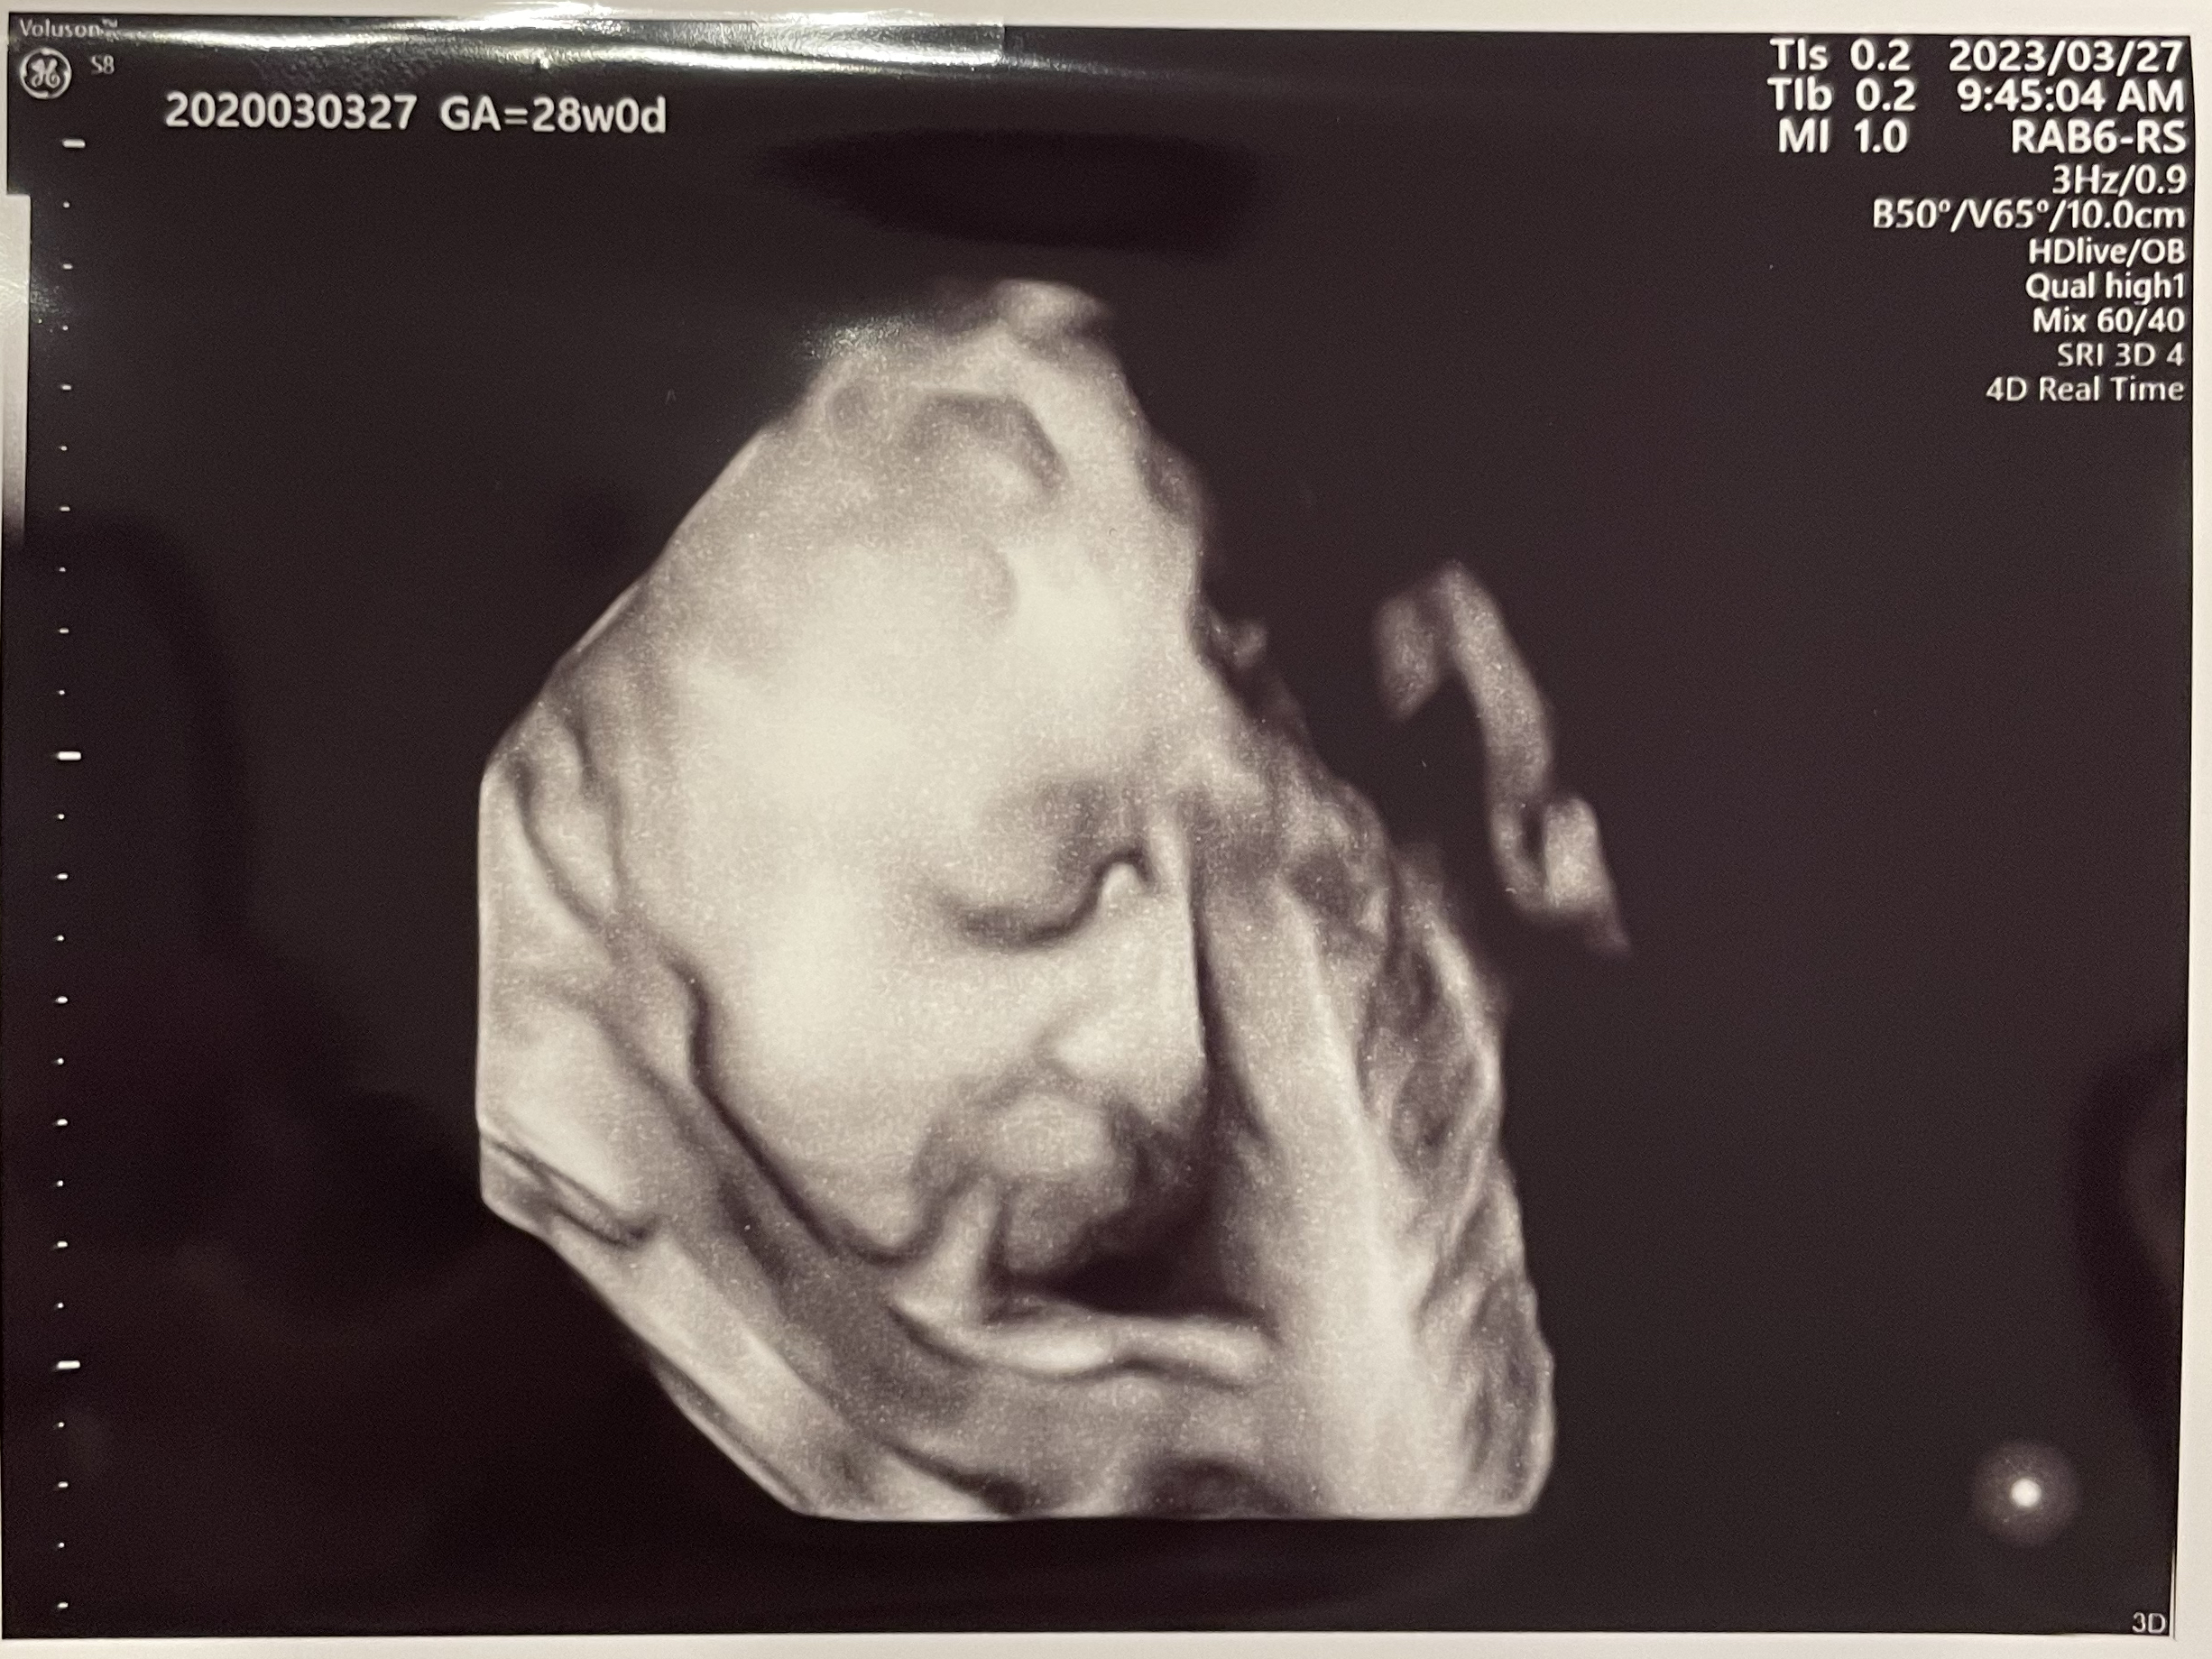

経腹エコー(4D)

本日もいつも通り、普通のエコーと4Dのエコーをしてもらいました。

逆子ではなくなっていました!実はあとから少し気になって、まだ指導前でしたが寝る前に何度か逆子体操をしていたんです。その甲斐あってか、妊婦健診当日の朝、お腹の中でぐるんぐるん動いているのがわかり、「パパに似てスケジュールをかなりきっちり守るタイプだな…」と思いました(笑)

成長も問題ないそうで「体重は平均です。まぁ、平均のちょっと上だね」と言われました。

2週間前が835gくらいだったので、今回1.2kgを超えていると思うとすごい成長!赤ちゃんってすごいですね。

4Dのエコーは録画されるので、録画をする最低時間が決まっているのか、結構長い間見せてくれます。

といってもお顔がメインで、お顔を数分間眺めている感じ。

今回のエコー写真では、口に何かくわえている?!と思ったのですが、「これはおそらく臍帯だね」とのことでした。超音波の映像なので、臍の緒をくわえているというよりは、重なっていてうまく写っていない感じだと思いました。

わりと鮮明に顔が見られるようになってきましたが、外見でわかる異常はなさそうなので安心しています。